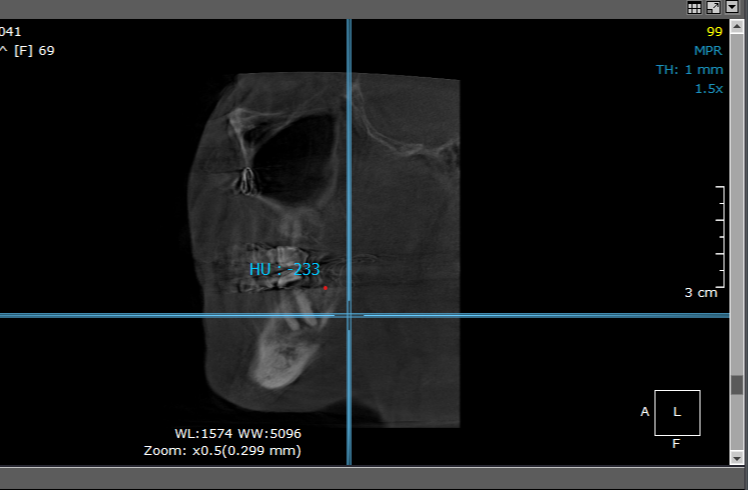

- Diagnosing Cavitations with Confidence: Understand the latest science, clinical signs, imaging interpretation, and diagnostic workflows.